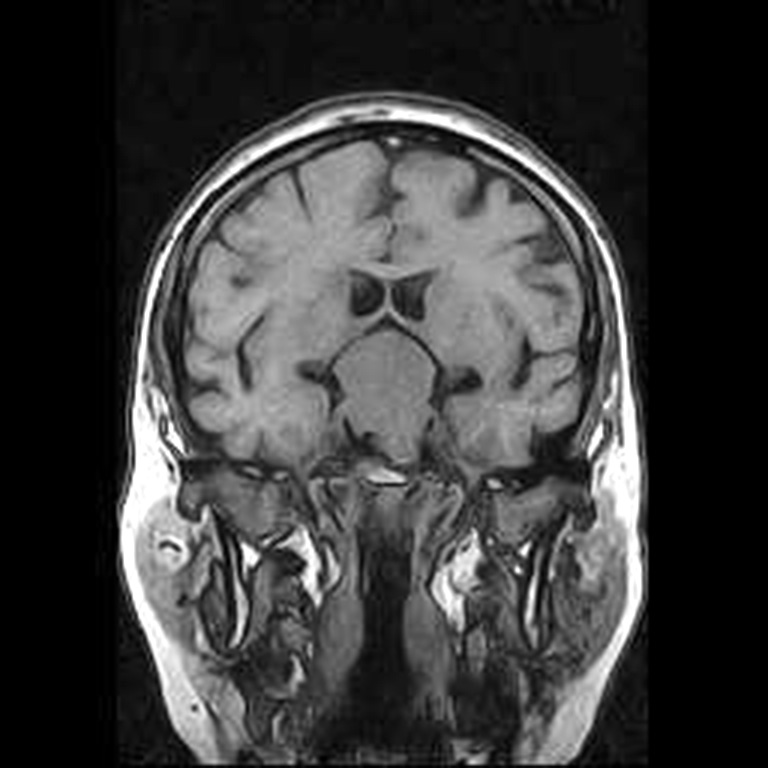

A B

Fig. 2. Patient P., 64 years old, HIPA with suprasellar extension, central chiasmal position. Brain MRI: A – coronal projection; B – sagittal projection